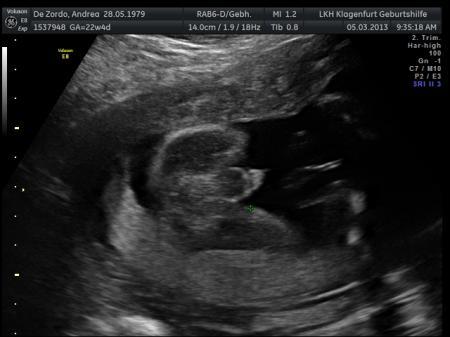

Hy Also ich kann da noch nicht sehr viel erkennen, naja aber ich hab auch ein Bild vom Pullermann bekommen, da sieht mann es noch genauer..

Bild zu

Auf dem Bild sieht man doch nur die Nabelschnur, aber ich denke wenn sie es eindeutig gesehen hat kann man da schon relativ sicher sein. Ich würde aber den nächsten Ulltraschall abwarten und schauen ob es sich dann nochmal bestätigt. Hier ist noch ein Bild von unserem Sohn, allerdings in der 21 Woche